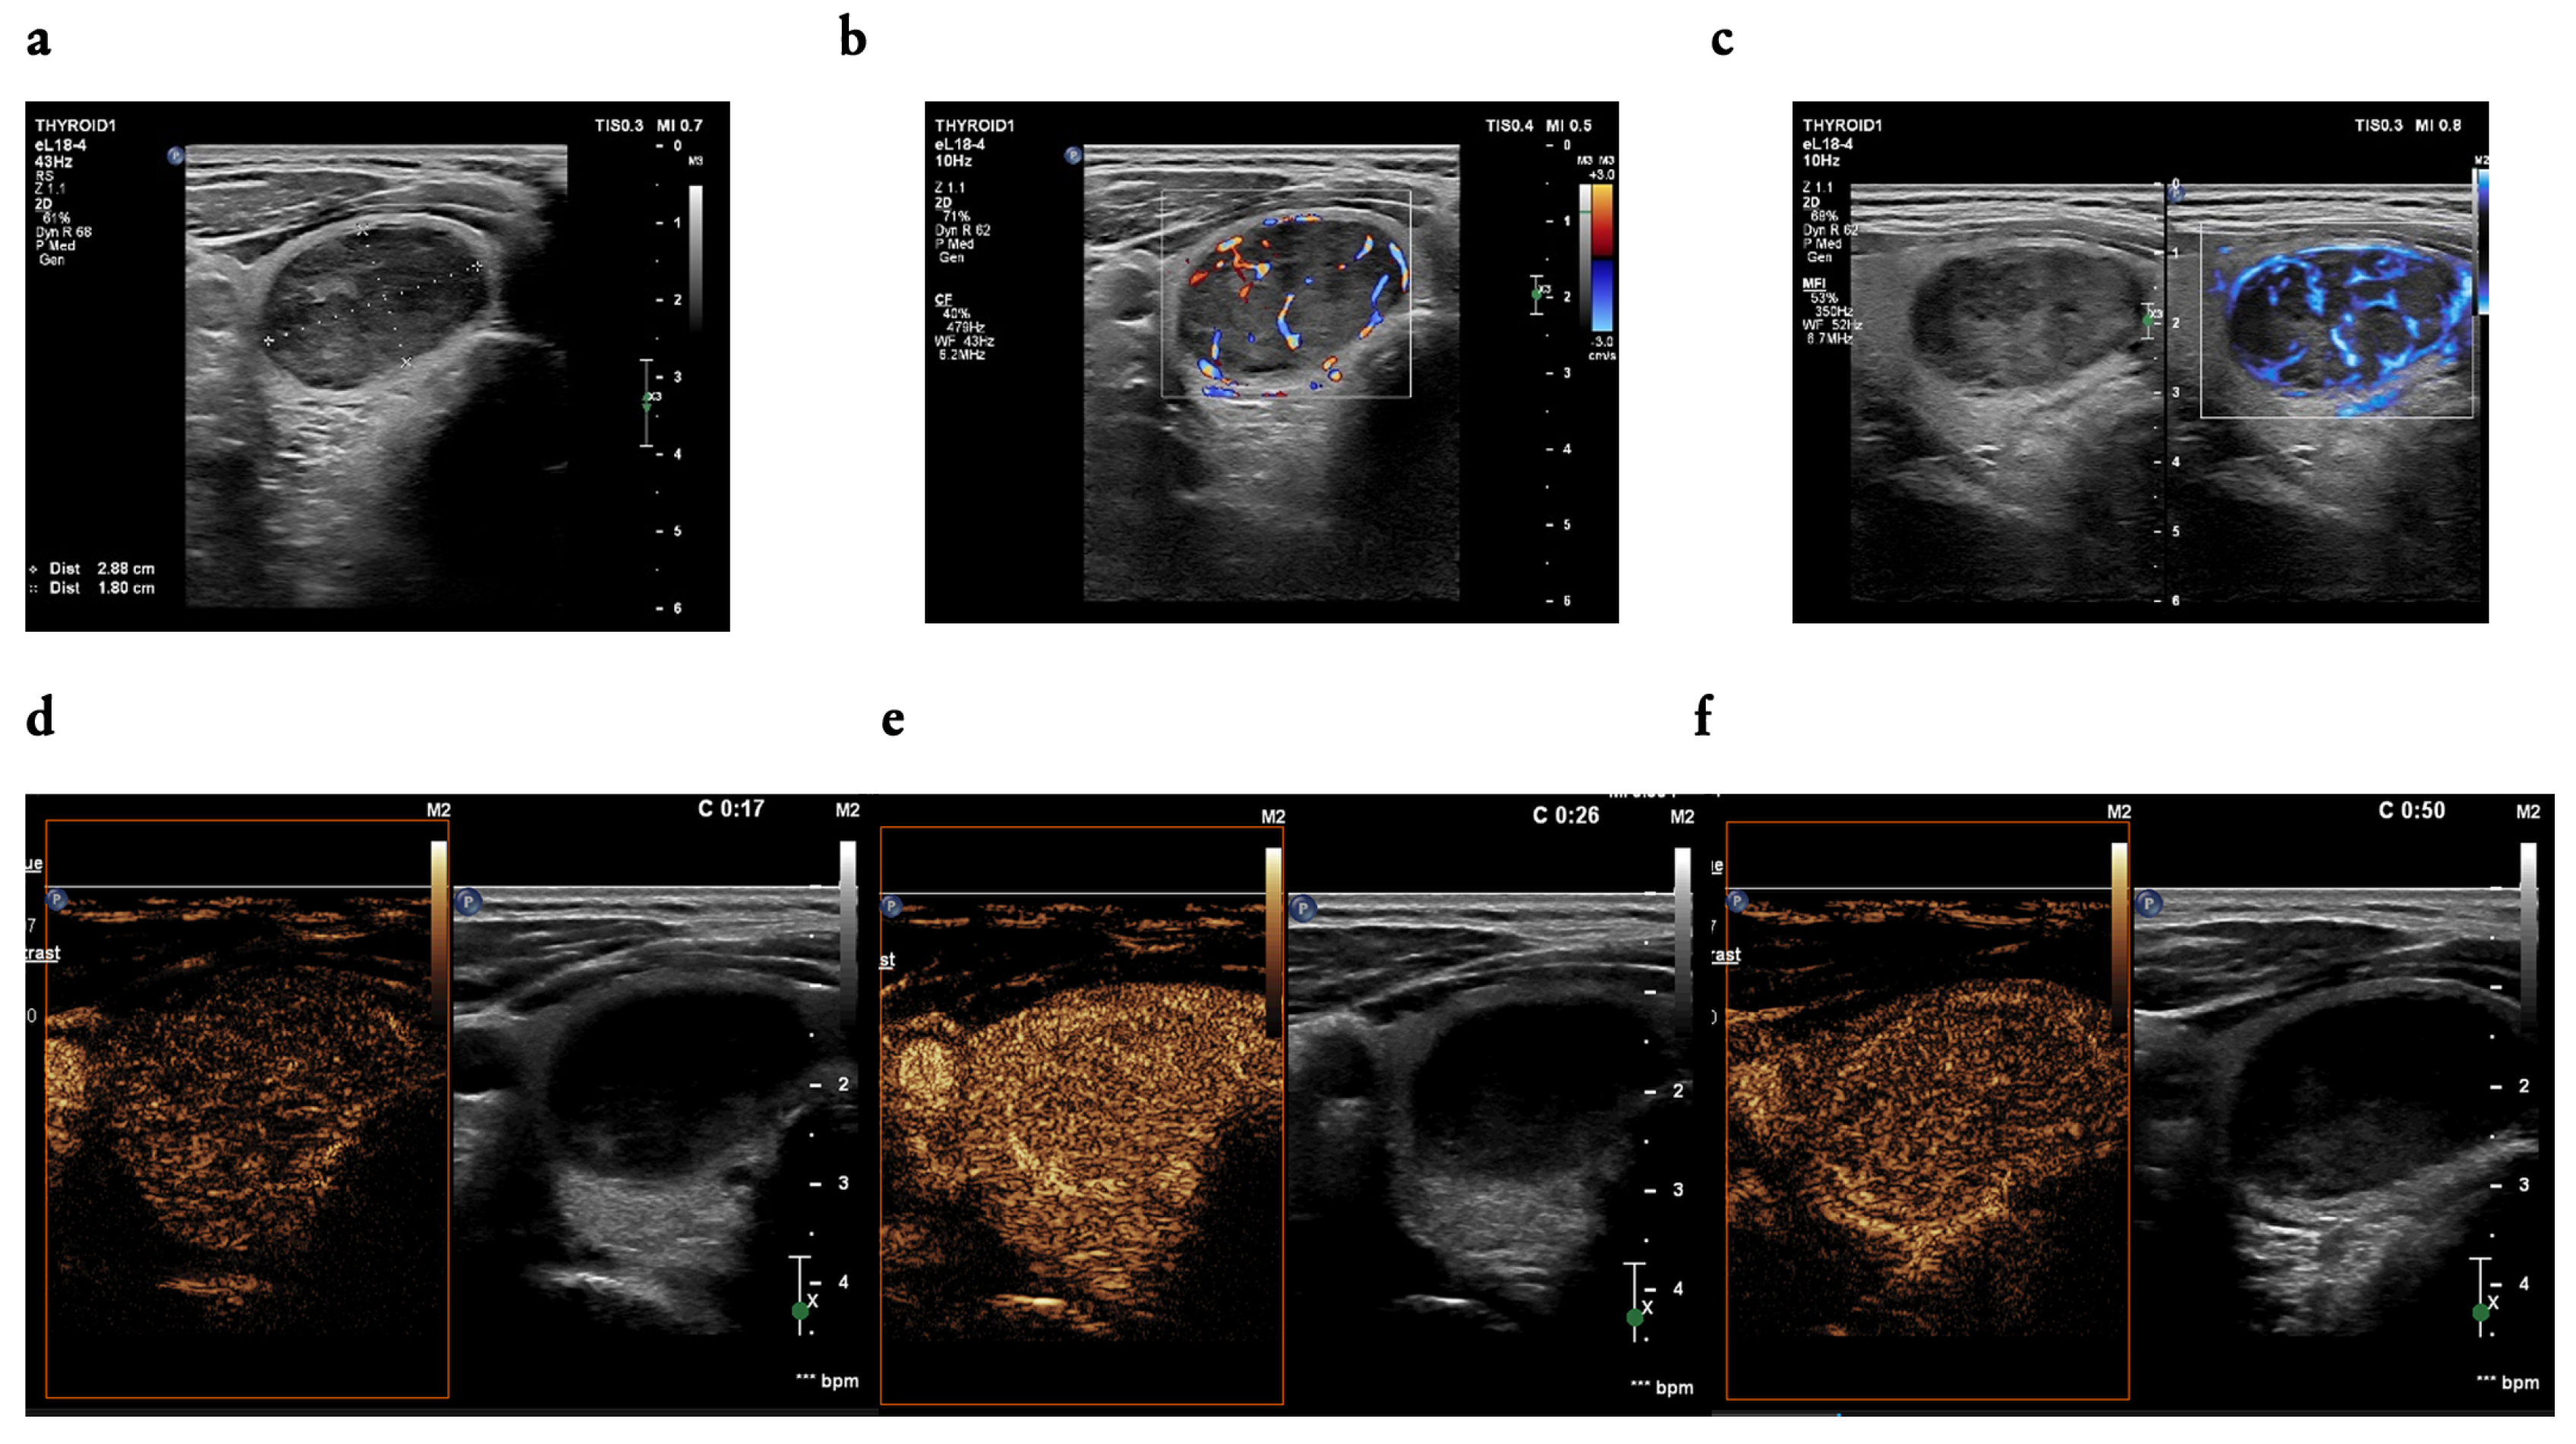

3.2. B-Mode Findings

3.3. CEUS Findings

4.4. The Utility of CEUS Patterns Assessed in the Study in Line with the Literature Review—Malignant Nodules

4.5. The Utility of CEUS Patterns Assessed in the Study in Line with the Literature Review—Benign Nodules